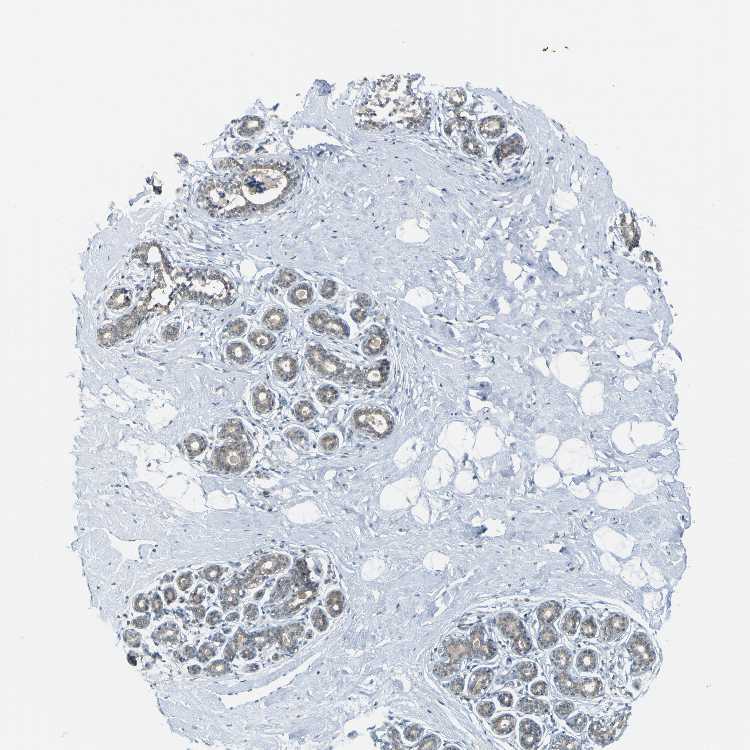

BREAST - Antibody stainingi

Antibody staining in the annotated cell types in the current human tissue is reported as not detected, low, medium, or high, based on conventional immunohistochemistry profiling in selected tissues. This score is based on the combination of the staining intensity and fraction of stained cells.

Each image is clickable and will lead to virtual microscopy that enables deeper exploration of all samples and also displays staining intensity scores, fraction scores and subcellular localization as well as patient and tissue information for each sample.

Antibody HPA011332Antibody CAB009661

Adipocytes Not detectedNot detected

Glandular cells MediumLow

Myoepithelial cells Not detectedLow